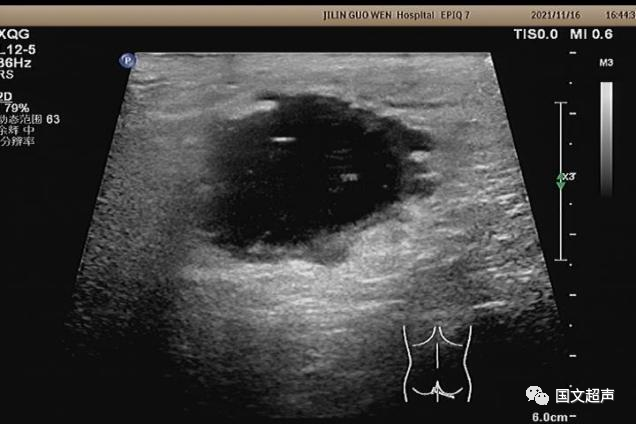

超聲檢查所見:

肛周:7點(diǎn)鐘方向皮下脂肪層內(nèi)探及不均質(zhì)低無回聲包塊,范圍約4.6*3.0cm,較淺處距體表約0.6cm,邊界不清,周圍軟組織回聲增強(qiáng),CDFI:周邊血流信號(hào)豐富,輕加壓探頭有涌動(dòng)感,如下圖: